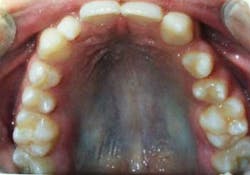

The following case study shows a Caucasian male, age 15 at the beginning of treatment. He had a peg lateral incisor No. 7 and was congenitally missing tooth No. 10. The treatment plan consisted of positioning tooth No. 7 for a veneer and opening space for an implant to replace tooth No. 10. After 30 months of orthodontic treatment had elapsed, there was still insufficient room for implant placement. There was sufficient room for the crown of No. 10, but the roots of teeth Nos. 9 and 11 were still too convergent to allow implant placement. The patient was leaving for college soon and was anxious to have treatment completed. The decision was made to have a periodontist do a corticotomy surgery to accelerate the tooth movement.

Corticotomy surgery was done and distal root movement was initiated on tooth No. 11 using a lever arm and elastic power chain. Root divergence was accomplished in eight weeks, and implant placement was accomplished at that time. The occlusion was detailed and orthodontic appliances were removed a short time later.